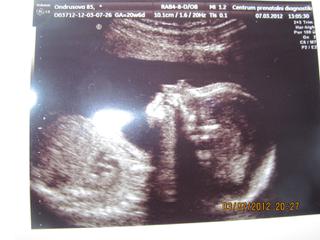

@saminomimino-Moc gratuluji k holčičce je hezká na fotečce a dost dobrá zprávička. 🙂

@saminomimino no velika gratulka,.. 🙂 fotecka krasna,,